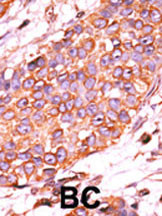

The anti-DUSP13 Pab (Cat. APR14320G) is used in Western blot to detect DUSP13 in human CEM lysate.

Formalin-fixed and paraffin-embedded human cancer tissue reacted with the primary antibody, which was peroxidase-conjugated to the secondary antibody, followed by AEC staining. This data demonstrates the use of this antibody for immunohistochemistry; clinical relevance has not been evaluated. BC = breast carcinoma; HC = hepatocarcinoma. |